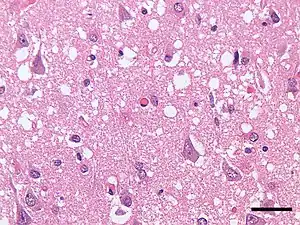

Micrograph showing spongiform degeneration (vacuoles that appear as holes in tissue sections) in the cerebral cortex of a patient who had died of a prion disease (Creutzfeldt-Jakob disease). H&E stain. Scale bar = 30 microns (0.03 mm).

Prions cause neurodegenerative disease by aggregating extracellularly within the central nervous system to form plaques known as amyloids, which disrupt the normal tissue structure. This disruption is characterized by "holes" in the tissue with resultant spongy architecture due to the vacuole formation in the neurons.[66] Other histological changes include astrogliosis and the absence of an inflammatory reaction.[67] While the incubation period for prion diseases is relatively long (5 to 20 years), once symptoms appear the disease progresses rapidly, leading to brain damage and death.[68] Neurodegenerative symptoms can include convulsions, dementia, ataxia (balance and coordination dysfunction), and behavioural or personality changes.